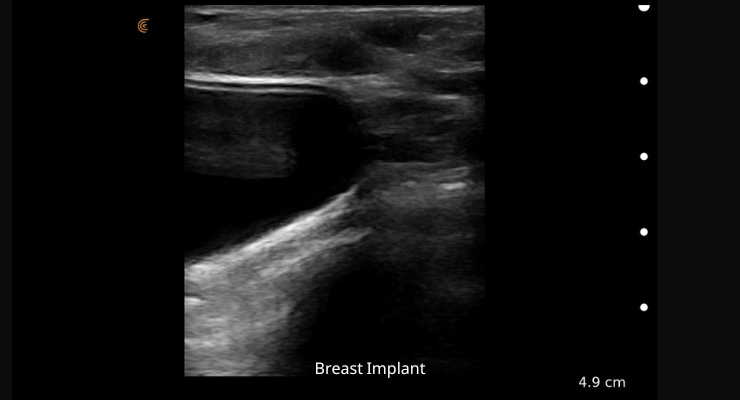

• תמונה חדה וברורה של רקמת השד

• הערכה, זיהוי וטיפול טוב יותר במשתל שד, ריפליניג קפלים ועוד